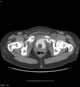

Air cystogram

Gas in bladder wall or lumen